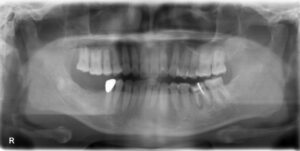

上下顎オールオン6症例

BEFORE AFTER 63歳男性/上顎6本・下顎6本 【治療内容】 全体的に歯が揺れてお食事がとりづらくなり、来院さ…